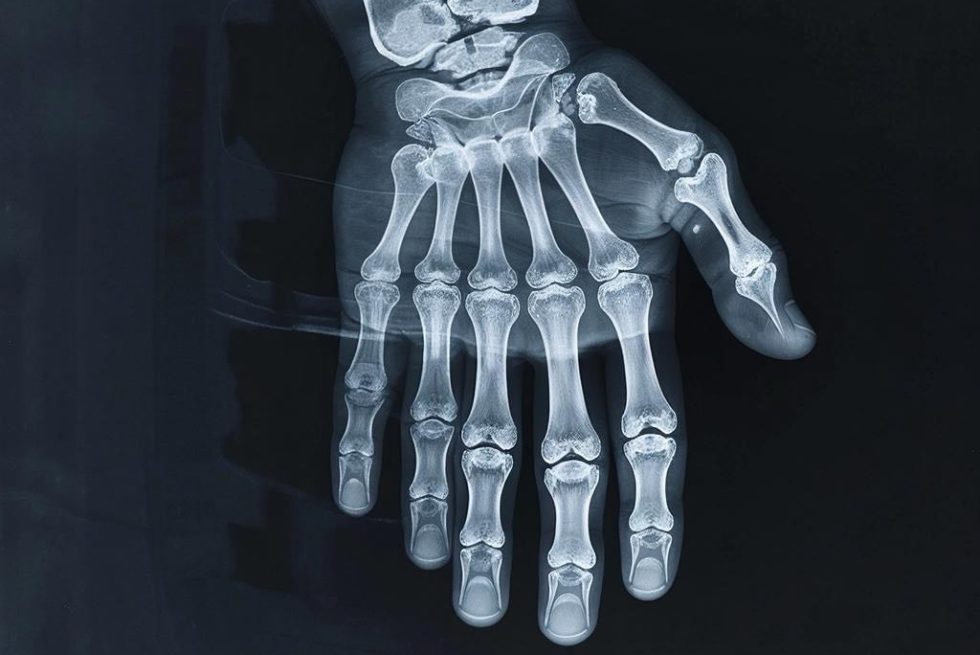

Применение рентгена началось сразу: в январе 1896 года врачи диагностировали переломы и удаляли пули. Во время Первой мировой Мария Склодовская-Кюри создала мобильные рентген-станции на автомобилях для фронта. Сегодня это ключевой метод выявления травм, болезней лёгких и проблем опорно-двигательного аппарата.

Рентген не читает мысли, но раскрывает скрытое. Криминалисты быстро его освоили: лучи находили пули и осколки в телах, а анализ трещин костей указывал траекторию выстрела. Сегодня рентгеновская спектрометрия выявляет микроследы (копоть, порох) без повреждения улик.